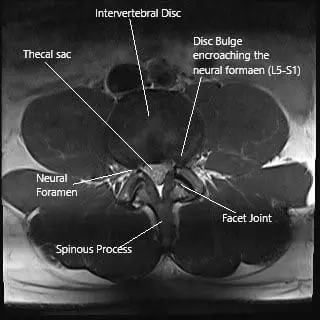

Axial section of the spine at L5-S1 level on an MRI